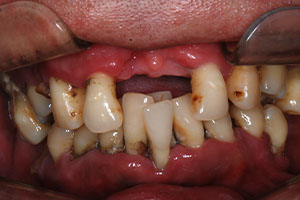

치료증례 전후사진

Before & After